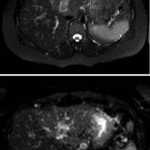

En este caso, presentamos una paciente femenina de 43 años de edad con antecedente de uso de ACO, a quien se le diagnosticó Trombosis portal mediante TC de abdomen c/cte. EV y trombofilia con mutación en el factor II de protrombina 20210, con evolución favorable.

Paciente femenina de 43 años, antecedente de obesidad grado I. Medicación habitual uso de ACO. Antecedente quirúrgico: una cesárea. Presenta cuadro clínico caracterizado por epigastralgia súbita de moderada intensidad. Se automedica con Buscapina sin mejoría del cuadro, por lo que acude a guardia. Le realizan TC y la derivan con diagnóstico de trombosis portal de la rama izquierda.

Se solicita nueva tomografía para descartar progresión de la trombosis y se vuelve a instaurar analgesia y anticoagulación EV.

Hallazgos imagenológicos